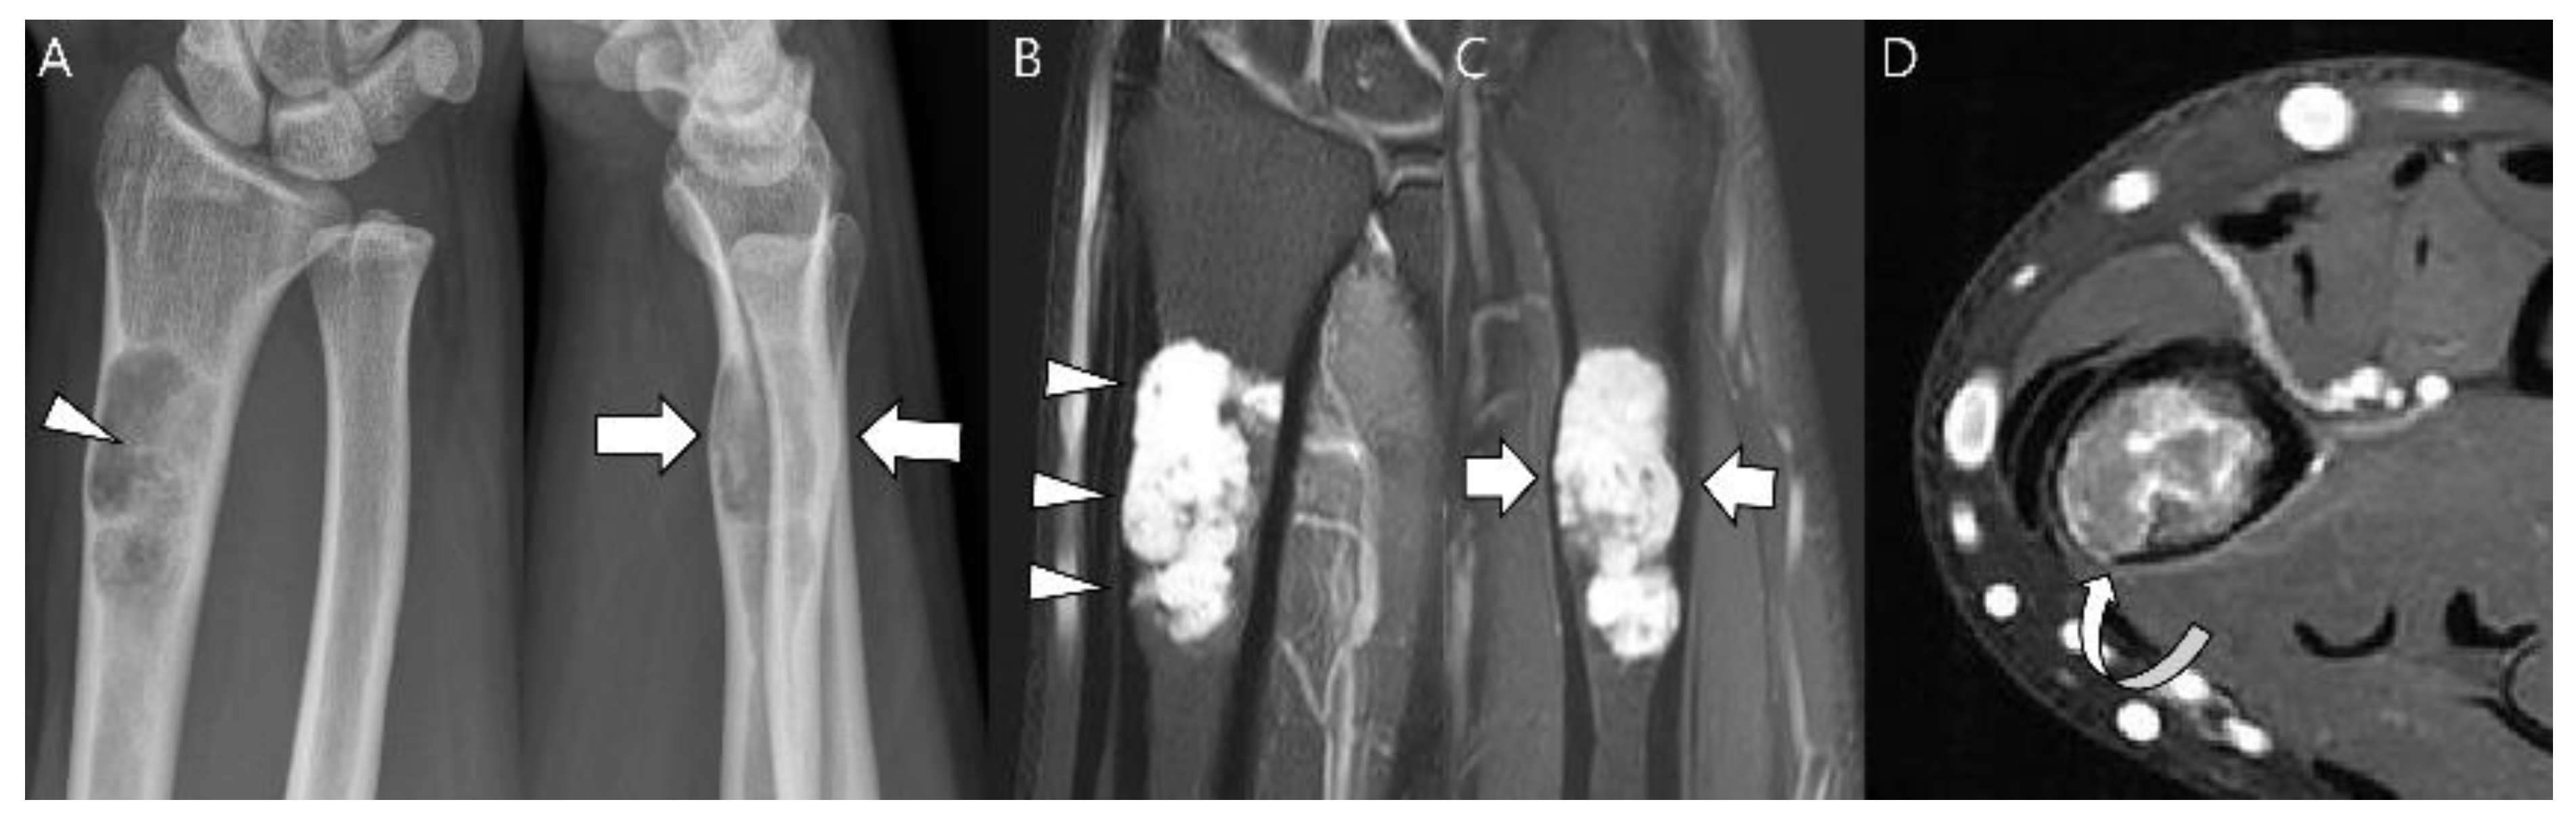

Figure 17.

A 35-year-old man presenting with wrist pain. (A) Plain radiographs reveal a lobulated lytic lesion with chondroid matrix mineralization (arrowhead) and bone expansion (arrows) in the distal radius. (B,C) Coronal and sagittal T2-weighted fat-suppressed images show an intramedullary high signal mass with deep and extensive endosteal scalloping (arrowheads) and bone expansion (arrows). (D) Axial T1-weighted enhanced image shows peripheral rim and septal enhancement. Note the volar cortical thinning or defect (curved arrow). This lesion was noted as an atypical cartilaginous tumor at the initial incisional biopsy but was revealed as chondrosarcoma grade 2 at extended curettage.